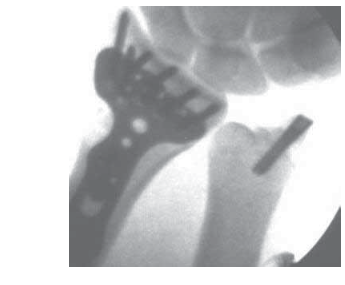

Arthroscopic Reduction and Fixation of Distal Radius and Ulnar Styloid Fractures DEFINITION ■ A bimodal ag…

RADIAL STYLOID FRACTURES ■ An isolated fracture of the radial styloid is an ideal fracture patte…